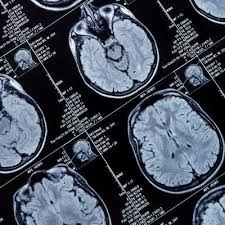

Artificial intelligence (AI) software developer Neurophet has secured U.S. Food and Drug Administration (FDA) 510(k) clearance for its Aqua brain MRI analysis software.

Aqua analyzes atrophy in the brain that's tied to neurodegenerative diseases such as Alzheimer's disease, according to the vendor. Neurophet said that Aqua can segment and analyze brain images in five minutes regardless of race, age, or gender.